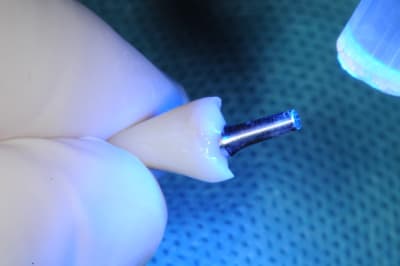

1)2) pilier impactable :ici c'est un 7° mais ils existent en 0, 7, 15 et 23°

5)6) essayage couronne provisoire

7) résine tab 2000

8) mise en place et durcissement